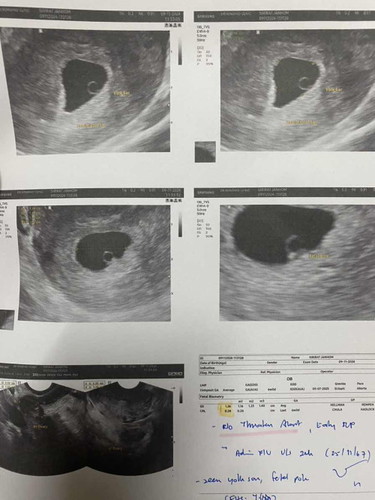

6 สัปดาห์ เห็นแต่ถุงตั้งครรภ์

หมอนัด 20 นี้ ได้ 8สัปดาห์ แม่ลุ้นใจจะขาด กลัวจะท้องลมค่ะ เพราะมีตกขาว เลือดออกช่วง6สัปดาห์ คิดหนักเลยค่ะ หมอบอกว่าเด็กยังอยู่ดี มารอดูหัวใจแม่ก้อลุ้น คิดมากๆๆๆๆ😖